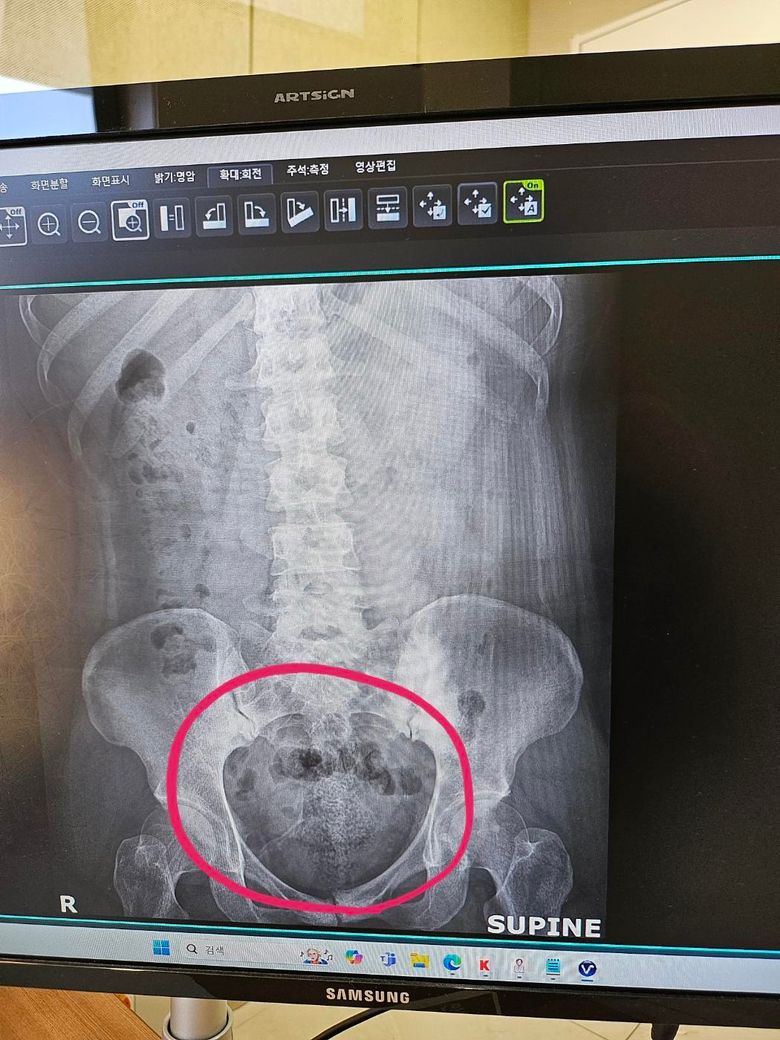

아랫배가 불편해서 엑스레이를 찍어봤는데 변이많이 차있다고 합니다 그런데 아랫부분 동그라미 쳐둔 부분에 변일 확률이 높다고하시는데

대변이 가득 차있어서 저렇게 보이는건가요?

변일 확률이 높다고 하는데.. 걱정이되서 다시 올려봅니다-

설명들으신대로 현재 복부 엑스레이에서 골반 부위에 보이는 공기 음영은 변으로 볼 수 있습니다.

직장 주변에 변이 차 있어서 힘드실 것 같기는 하네요. 아마 변이 딱딱한 상태에서 나오려고 하는데 잘 안나오니 불편할 겁니다. 일단 관장도 하고, 안되면 손가락으로 파내면 편해질 겁니다.